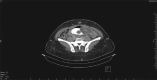

Retrograde jejuno-jejunal intussusception is a rare complication of bariatric surgeries. It causes acute sudden symptoms that require immediate surgical intervention. We report a case of a 46-year-old female who underwent Roux-en-Y gastric bypass (REYGP) 3 years prior. The patient presented to the emergency department with acute sudden abdominal pain, nausea and vomiting. Laparoscopically, intussuscepting small bowel segment was found gangrenous, and it was resected and end-to-end anastomoses were fashioned. The postoperative course was uneventful, and the patient remained asymptomatic for the 12 months of follow-up. Patients with retrograde intussusception experience an intolerable severe pain that necessitates surgical intervention. The etiology of intussusception as a complication after REYGP is unclear, yet theoretically some possible etiologies exist. The initial diagnosis of retrograde intussusception is made based on abdominal computed tomography. Early intervention significantly reduces morbidity and mortality.